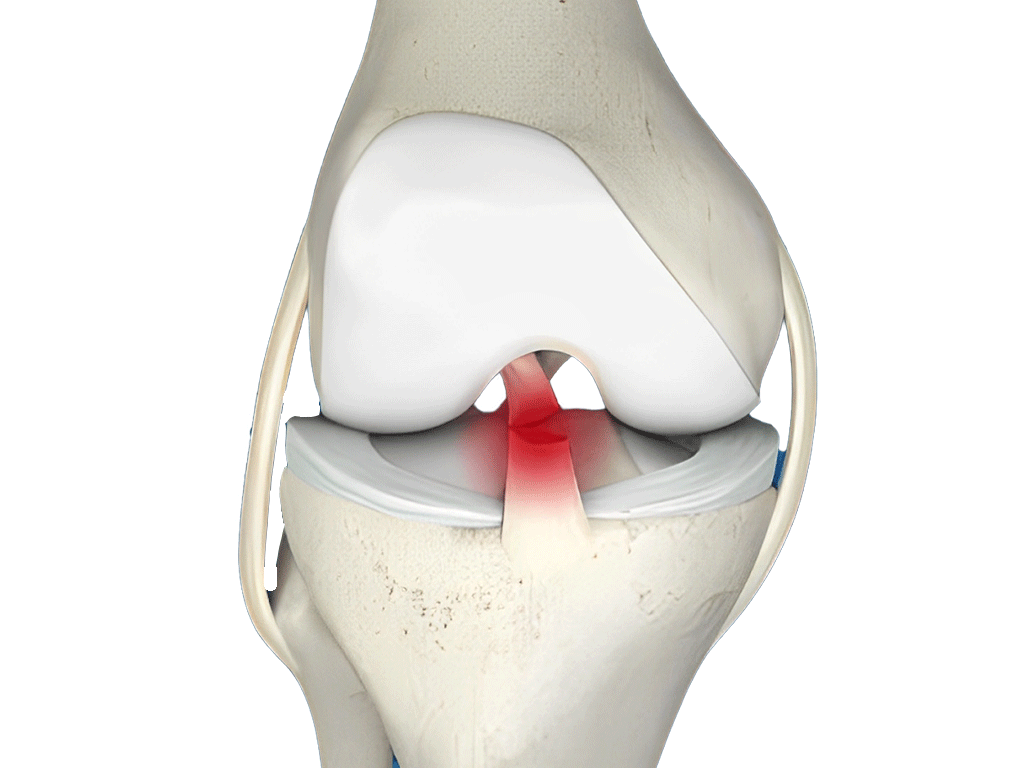

Knee

Cartilage tear

- Surgery for fractures or torn ligaments/tendons.